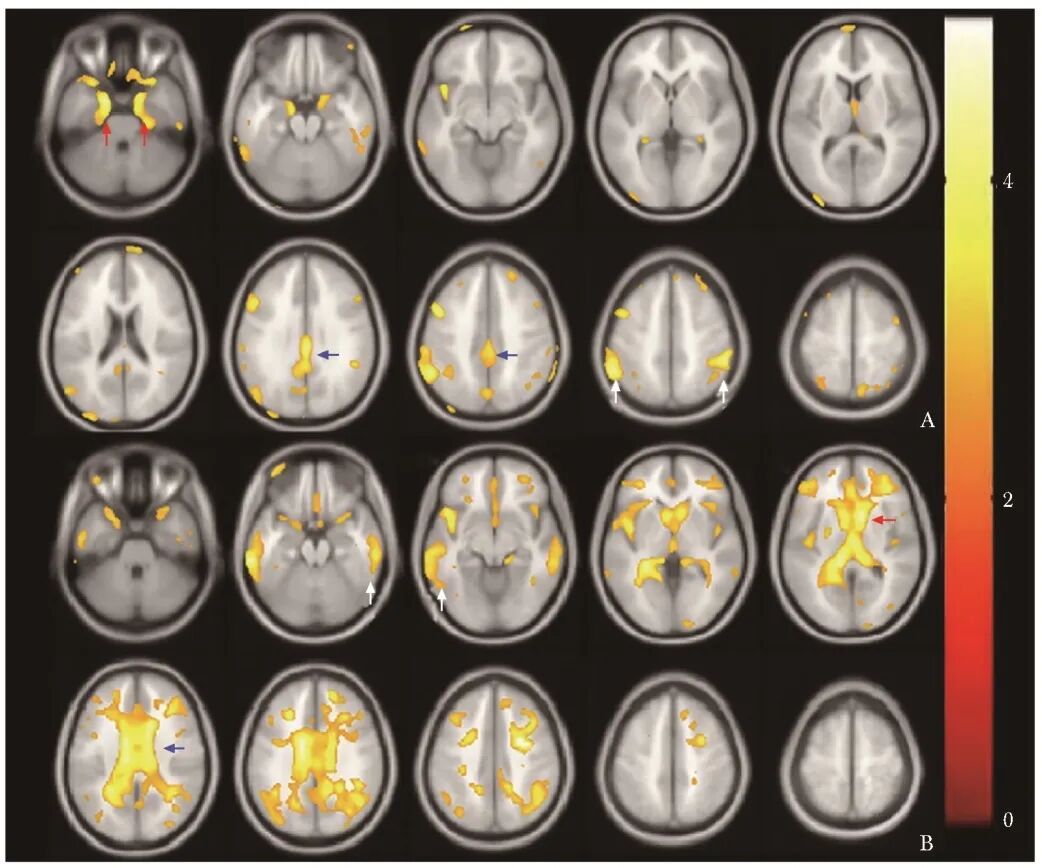

以P<0.01为显著性差异水平。相较对照组,AD组后扣带回、海马旁回、顶叶、颞叶内侧的代谢显著减低;CAA组广泛白质区以及尾状核头、胼胝体、前扣带回、颞叶外侧皮层等处代谢显著减低(图2)。

图2 AD和很可能CAA患者基于体素的脑代谢改变图像

A. AD患者颞叶内侧(红箭头)、后扣带回(蓝箭头)和顶叶背外侧皮层(白箭头)代谢减低;B.很可能CAA患者广泛白质区、尾状核头(红箭头)、胼胝体(蓝箭头)、前扣带回(蓝箭头)、颞叶外侧皮层(白箭头)代谢减低

AD、CAA:同图1